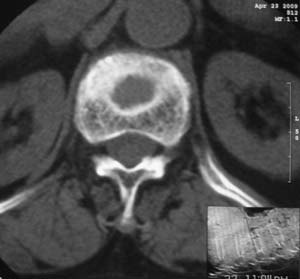

患者,女,72岁,胸背部疼痛3月余,无明显外伤史。曾应用局部封闭、非甾体类止痛药治疗效果不明显,近来疼痛缓解频感背困,平卧缓解,近日行ct检查发现胸12椎体病变,烦请同道发表意见,诊断什么?有何治疗经验!谢谢!!!

标绘图示:第十二胸椎级第一腰椎椎体楔形改变。ct扫描示:第十二胸椎椎体骨质结构紊乱,并可见一囊状低密度影,边缘可见硬化,椎体皮质完整。

考虑:第十二胸椎陈旧性骨折、许莫氏结节。